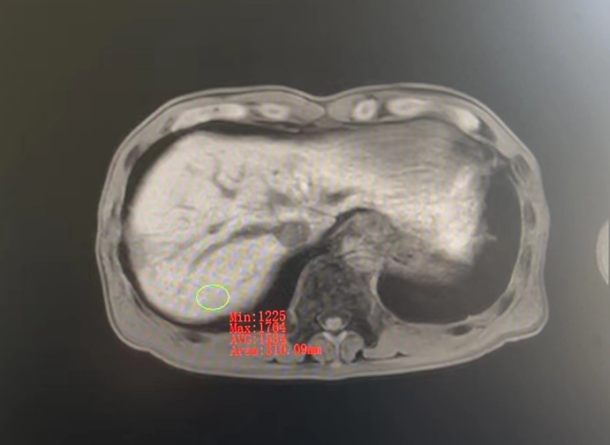

2019年肝癌复发时,肿块约有5cm大

对于这样手术后复发、普通放疗后复发的肿瘤,射波刀治疗是更优选择。为了进一步治疗,2019年1月,农先生来到我院就诊。结合MRI结果,医生确认疾病复发,并且复发病灶有射波刀治疗指征,立即为农先生制定射波刀治疗方案。农先生于当月便进行了3次射波刀治疗,过程顺利,不久后便出院了。